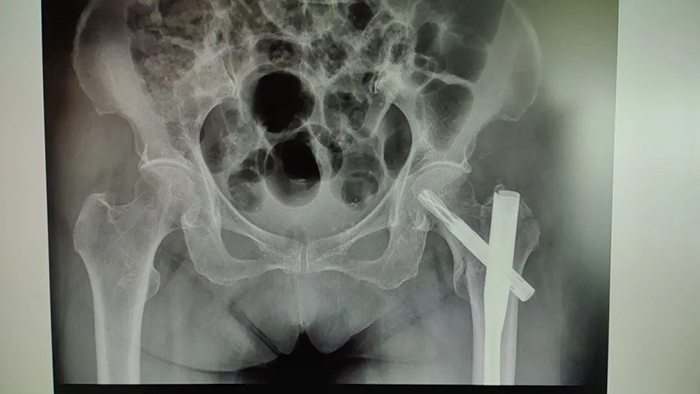

患者术前影像

虽说做手术是最有效的方式 但叶老太的手术风险很大 ◆患者血红蛋白水平较低,一旦出现手术创伤**,有可能引起消化道大出血,危及生命。 ◆患者年事已高,有高血压、冠心病、糖尿病等病史,对手术的耐受能力较差,手术并发症及手术切口不愈合、感染的风险大。 ◆患者重度骨质疏松,腰椎T值仅为-4.2,手术中轻轻一敲就有可能导致骨折劈裂。 面对复杂病情,医务科组织消化内科、血液科、手术麻醉科、心血管内科、内分泌科、中医骨伤科联合会诊,制定严谨的手术预案。 经过充分的术前准备,叶老太血红蛋白浓度补充到94g/L,陈瑞松副主任医师、冯安平主治医师为其进行左股骨粗隆间粉碎性骨折闭合复位内固定术。手术顺利完成,患者生命体征平稳。 患者术后影像 术后 中医骨伤科医护团队精心护理 叶老太恢复良好 目前已出院回家休养 ▲出院时,患者及家属向中医骨伤科医护团队送来锦旗表达感谢。 如果老人有髋部骨折方面的困扰 可至我院中医骨伤科进一步咨询 中医骨伤科出诊专家一览表